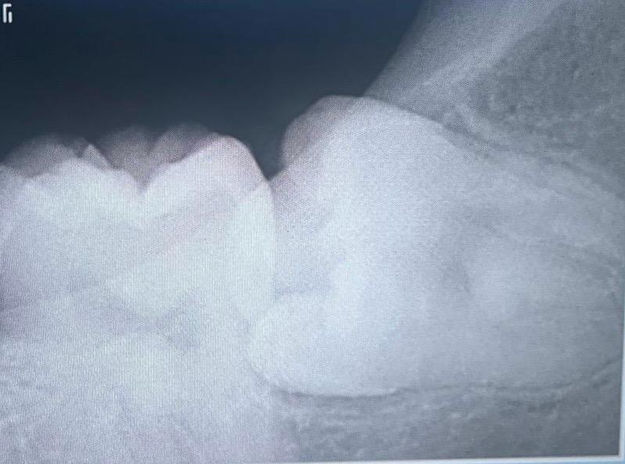

Ya sea que necesites una extracción de tercera molar, la colocación de implantes dentales, un injerto óseo o cualquier otro procedimiento quirúrgico, puedes tener la certeza de que estarás en manos expertas y cuidadosas. Cada tratamiento es planificado con detalle, tomando en cuenta tus necesidades, tu salud y tu comodidad.

Puede detectar y tratar problemas que un dentista general podría pasar por alto, como quistes, tumores.

Si tienes dientes retenidos, muelas del juicio complicadas.